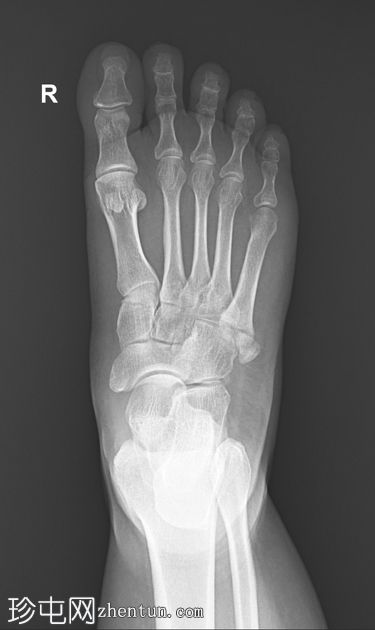

X线片

2.jpeg

斜位片

可见第五跖骨基底部粗隆(茎突)骨折。骨折线位于关节外,未延伸至第四至第五跖骨间关节。移位轻微。未见其他急性骨折。偶见腓骨副骨。